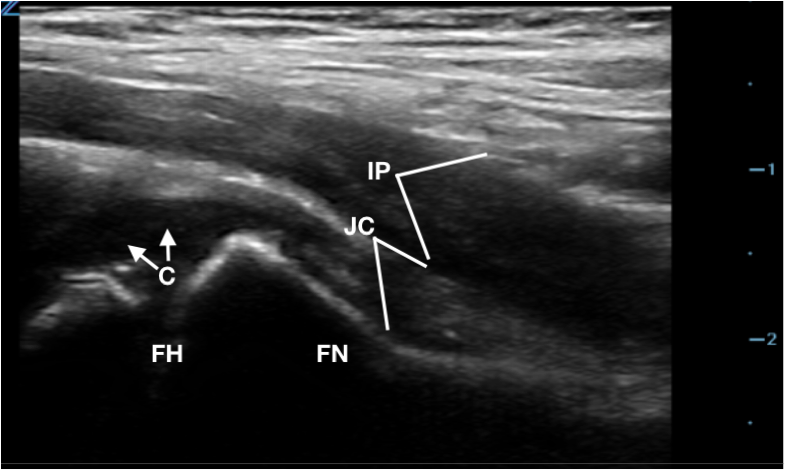

- Figure 2. Anatomy of hip joint on ultrasound (C: Cartilage/physis on femoral head, FH: Femoral Head, FN: Femoral Neck, JC: Joint Capsule, IP: Iliopsoas muscle)

- Measure thickness of joint (area from periosteum to outer joint capsule just deep to iliopsoas muscle) at the femoral neck.